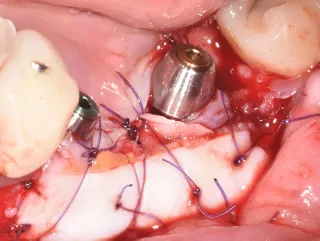

3 . Split bone block technique using autogenous cortical plates taken from the left ramus according to F. Khoury's protocol.

One buccal plate and one lingual plate are positioned and osteosynthesised with 1 mm Stoma screws.

4. Forming and filling the gap with a mixture of autogenous/xenogeneic bone mixed with PRF (sticky bone).